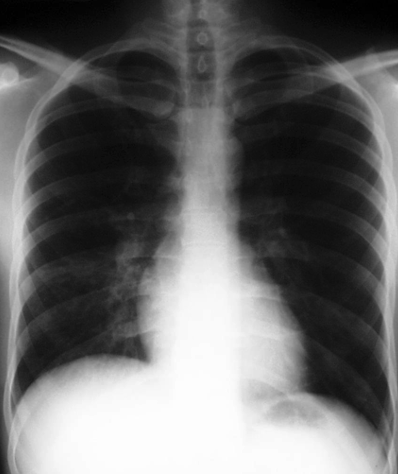

8

What is the systematic order of approach for chest x-ray assessment?

A

1. Bony framework

2. Soft tissues

3. Lung fields and Hila

4. Diaphragm and pleural spaces

5. Mediastinum & heart

6. Abdomen and neck